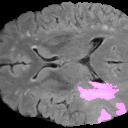

Weakly Supervised Semantic Segmentation (WSSS) relying only on image-level supervision is a promising approach to deal with the need for Segmentation networks, especially for generating a large number of pixel-wise masks in a given dataset. However, most state-of-the-art image-level WSSS techniques lack an understanding of the geometric features embedded in the images since the network cannot derive any object boundary information from just image-level labels. We define a boundary here as the line separating an object and its background, or two different objects. To address this drawback, we are proposing our novel ReFit framework, which deploys state-of-the-art class activation maps combined with various post-processing techniques in order to achieve fine-grained higher-accuracy segmentation masks. To achieve this, we investigate a state-of-the-art unsupervised segmentation network that can be used to construct a boundary map, which enables ReFit to predict object locations with sharper boundaries. By applying our method to WSSS predictions, we achieved up to 10% improvement over the current state-of-the-art WSSS methods for medical imaging. The framework is open-source, to ensure that our results are reproducible, and accessible online at https://github.com/bharathprabakaran/ReFit.